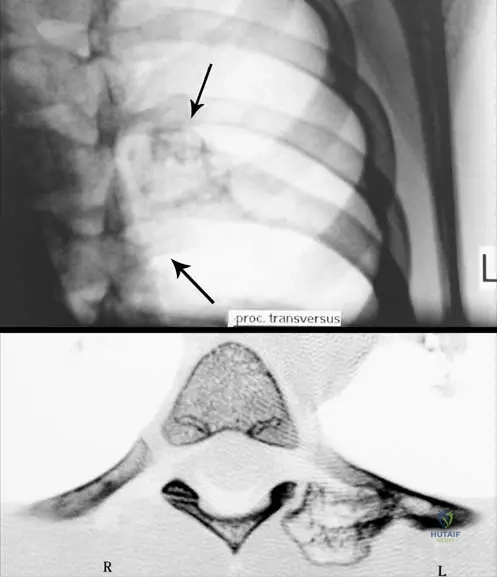

A 35-year-old male presents with a slowly growing mass on the posterior aspect of his distal femur. Radiographs reveal a heavily mineralized mass on the surface of the bone with a clear cleavage plane from the underlying cortex and no apparent medullary involvement. A CT scan confirms the absence of cortical or medullary continuity between the mass and the parent bone.

Rationale: Parosteal osteosarcoma typically presents as a heavily mineralized mass on the surface of the bone, most commonly on the posterior aspect of the distal femoral metaphysis, with no cortical or medullary continuity between the mass and the parent bone. This description perfectly matches the clinical vignette and radiographic findings. Conventional osteosarcoma is typically intramedullary and destructive. Periosteal osteosarcoma is a surface tumor but usually diaphyseal, partially mineralized, and may show malignant periosteal new bone formation. High-grade surface osteosarcoma is also on the surface but often shows more aggressive cortical involvement and incomplete mineralization. Chondrosarcoma would typically show chondroid matrix mineralization, not dense osteoid. The image (Fig. 8.69 a–c) clearly illustrates a parosteal osteosarcoma with its characteristic appearance.

Correct Answer: C